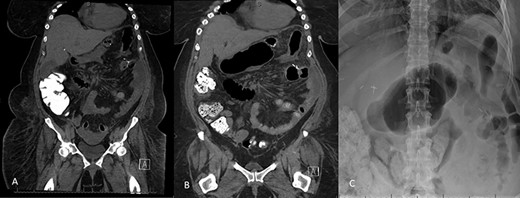

The patient is a 46-year-old female with a pre-operative body-mass index (BMI) of 48 kg/m2 who underwent an uneventful laparoscopic RYGB with a 50-cm biliopancreatic limb and 100-cm alimentary limb and an antecolic, antegastric-stapled gastrojejunostomy using a 21–3.5-mm circular stapler in addition to the repair of a small sliding hiatal hernia. A thick omentum was divided in the midline, starting at the level of the mid-portion of the transverse colon moving distally through the edge of the omentum (Fig. 1). The procedure was uneventful, and the patient was discharged home on postoperative day 1. She had a scheduled follow-up visit at 2 weeks and was progressing as expected. Three weeks postoperatively, she presented to the emergency room complaining of two-day history of severe, diffuse abdominal pain. Initial vital signs were normal and laboratory values were WBC of 6.7 109/L, creatinine 0.76 mg/dl and lactate of 1.2 mmol/L. CT scan was obtained (Fig. 2A and B) that demonstrated 17.7 cm partially encapsulated mixed attenuating area on the right side of her abdomen, suggestive of omental infarction with necrosis. There was no evidence of leak from GJ or JJ anastomoses on CT with oral contrast, which was subsequently confirmed on upper GI with small bowel through. She was admitted for observation. Over the course of the next day, she reported worsening abdominal pain and developed tachycardia to 117 and BP of 89/68 mmHg. Repeat WBC count was 12.7 109/L, creatinine 1.29 mg/dl and lactate of 5.0 mmol/L.

A and B: Abdominal and pelvic CT scan obtained at POD # 21 readmission for abdominal pain showing a 17.7-cm mixed attenuating lesion extending anterior to the transverse colon into the upper-pelvis-associated stranding and fluid level suggestive of omental infarction and liquefied necrosis.